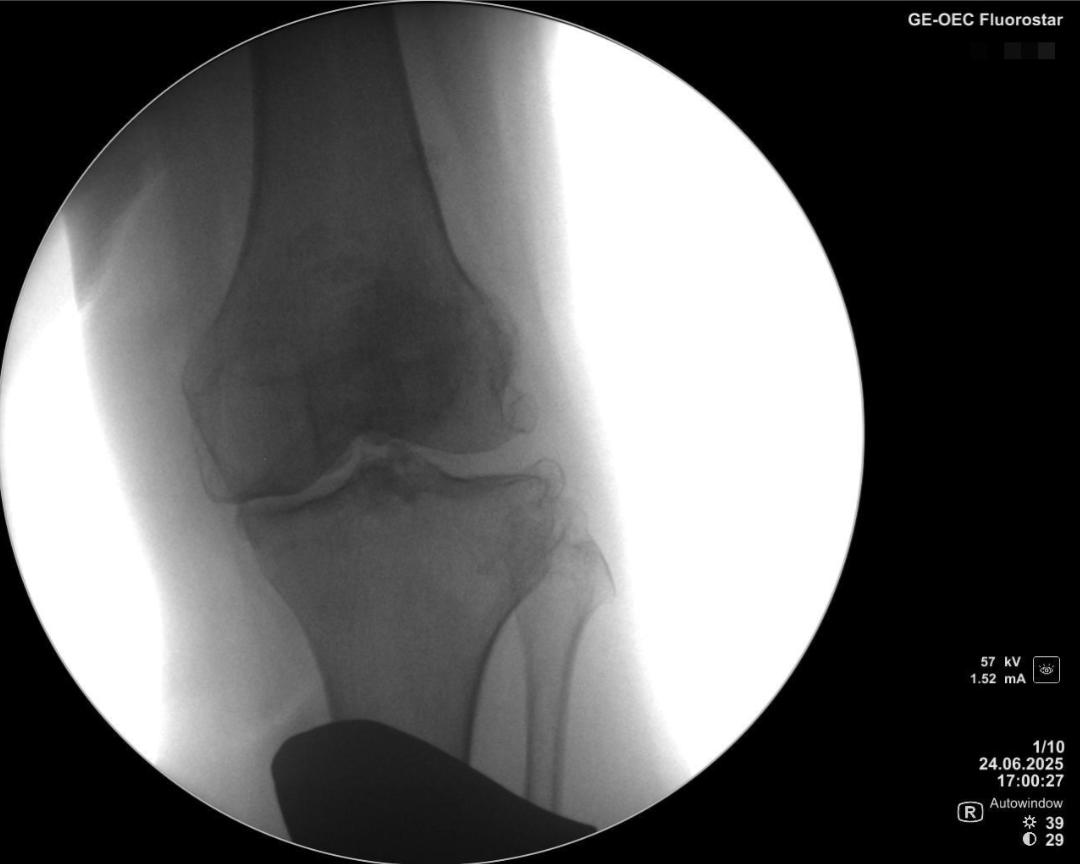

术前透视片

内翻应力位